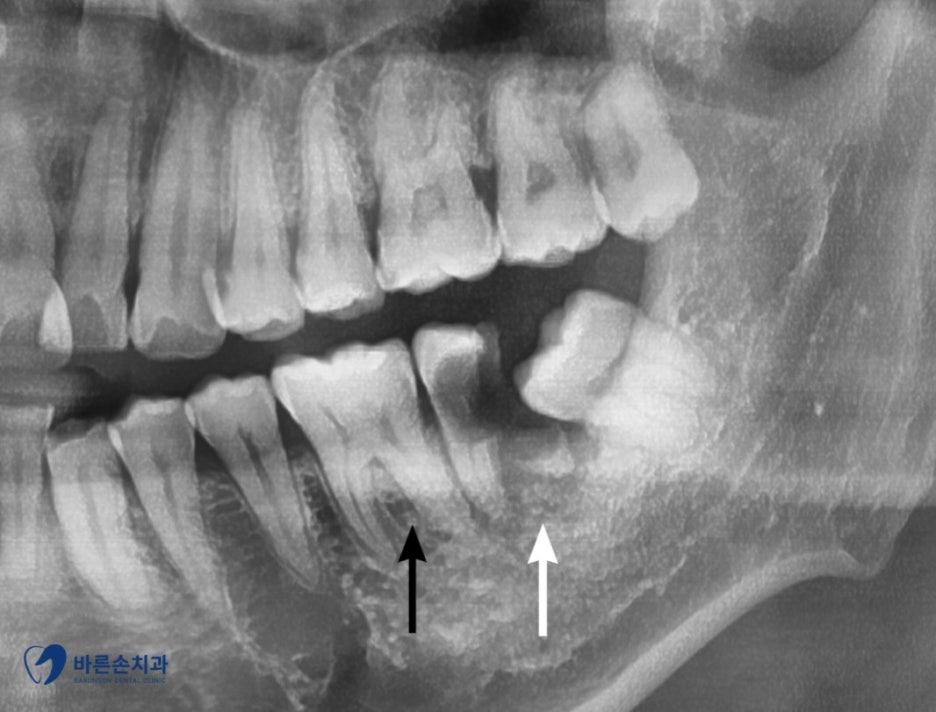

환자분이 불편함을 느낀 치아는 ‘하얀색’ 화살표로 가리킨 치아인데요,

정상적인 치아는 ‘검은색’화살표로 가리킨 치아처럼 치아의 머리 부분이 하얗게 남아있어야 합니다.

환자분의 치아는 엑스레이 상으로만 봐도 충치로 인해 치아가 많이 상실된 걸 확인하실 수 있는데요!

환자분 같은 경우에는 뒤에 사랑니가 기울어져 나면서 앞쪽 치아와 사랑니 사이에 음식물도 끼고

관리가 안 되어 충치가 생기신 경우입니다!